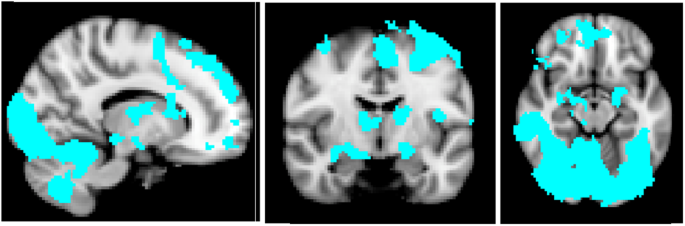

A Single Dose Of Fluoxetine Reduces Neural Limbic Responses To Anger In Depressed Adolescents Translational Psychiatry